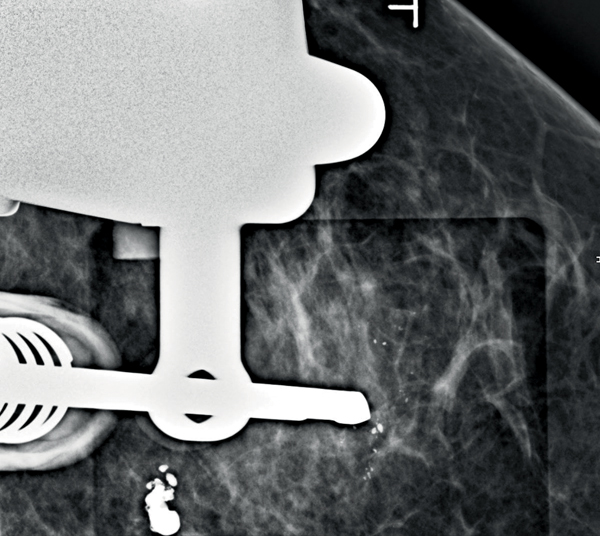

- Πρωτοποριακή στερεοτακτική εντόπιση και βιοψία μαστού με ή χωρίς τομοσύνθεση (HD tomo biopsy) που επιτρέπει στη στόχευση με ακρίβεια +/-1χιλιοστού, χρησιμοποιώντας την ευρείας γωνίας τομοσύνθεση (wide angle technology)

Απεικόνιση 1